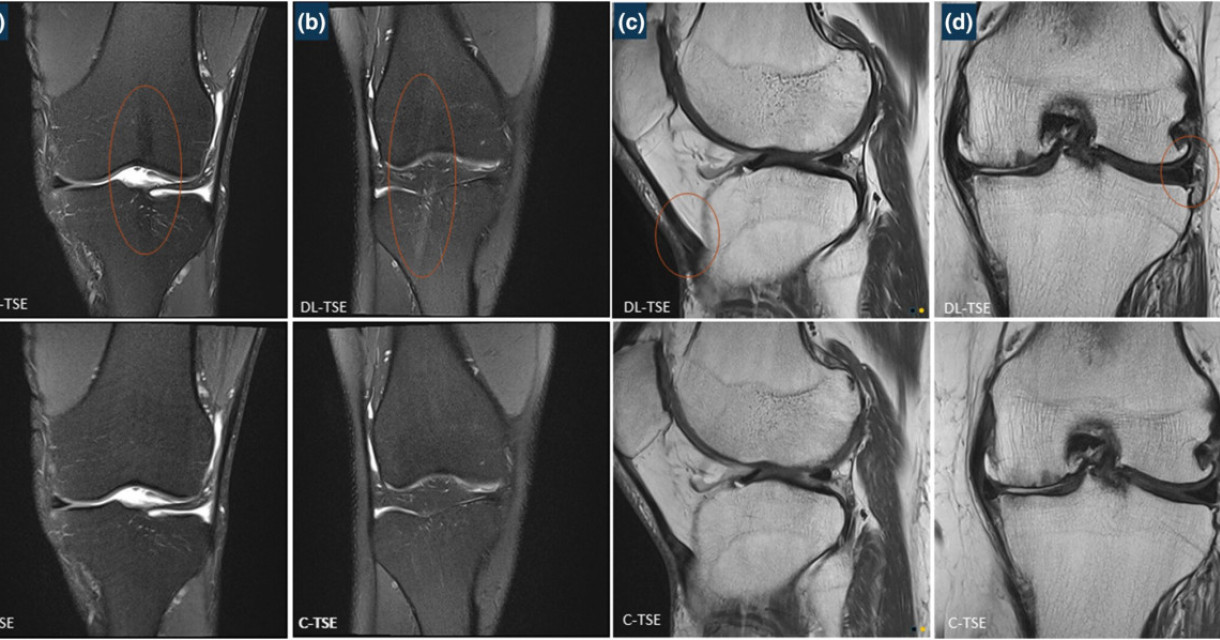

Deep-Learning TSE imaging can provide enhanced knee images

The study, titled “Evaluation of deep-learning TSE images in clinical musculoskeletal imaging”, compared the fat-saturated and non-fat saturated turbo spin echo (TSE) magnetic imaging knee sequences reconstructed conventionally against a deep-learning based reconstruction of accelerated TSE (DL-TSE) scans.

Overall, the radiologists who participated in this study preferred DL-TSE reconstruction. They found that using this method resulted in faster image acquisition times and enhanced spatial resolution while still preserving the image contrast. When using the DL-TSE reconstruction method, images were acquired 52% faster with an improved image resolution of at least 45%. Smaller structures in the knee were better depicted 60% of the time.